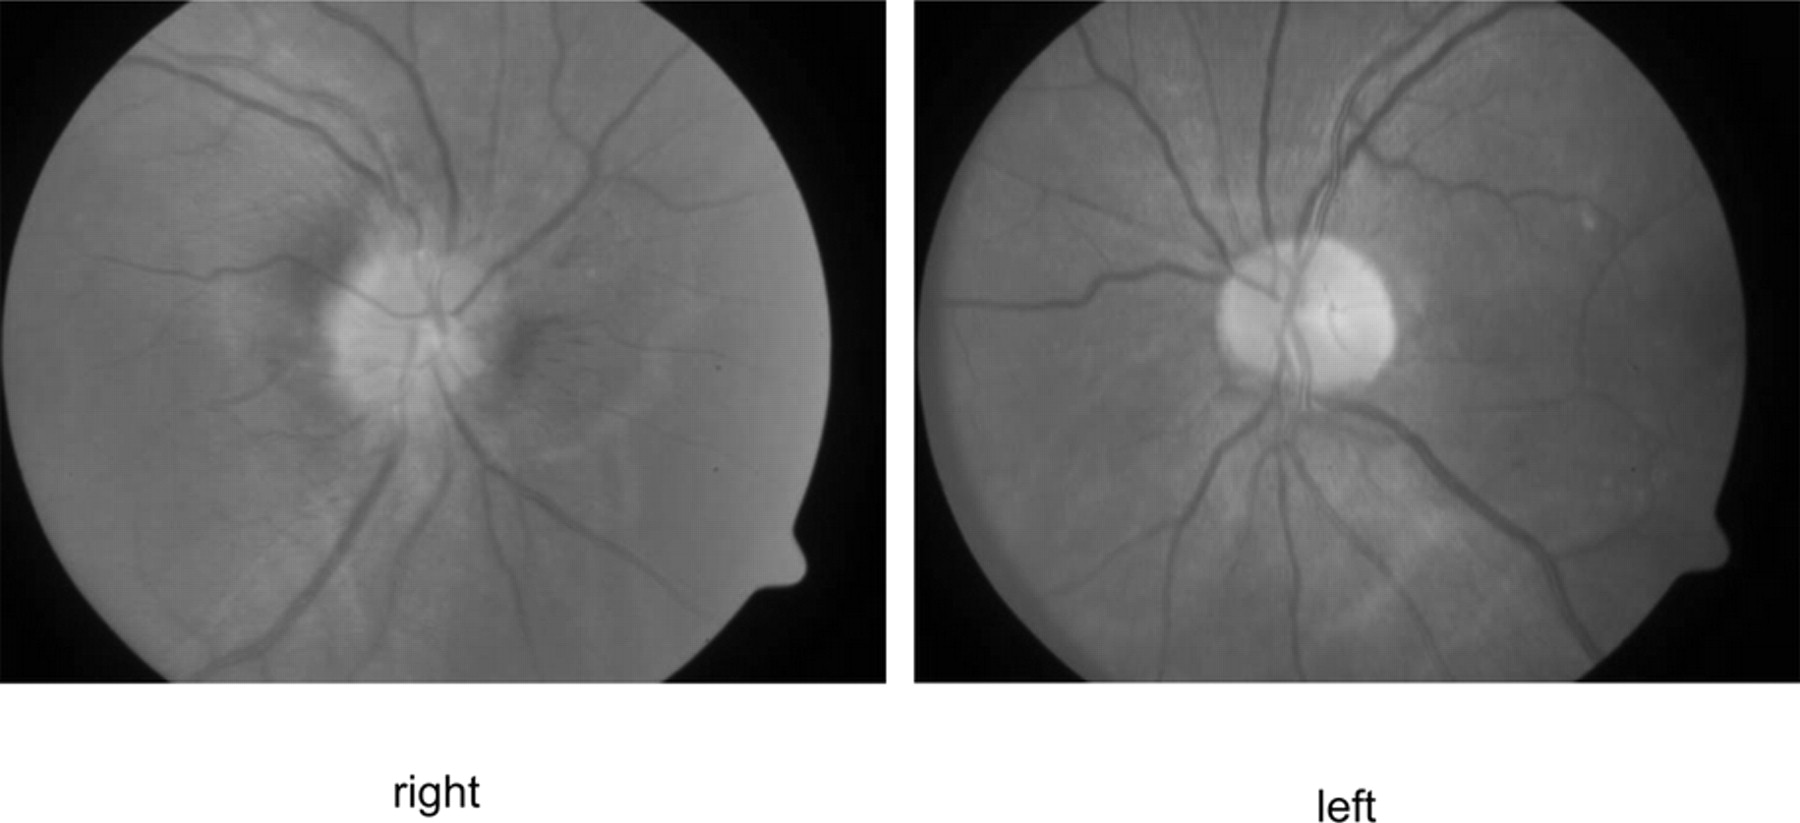

平均42岁男子,他的血压230/130毫米汞柱,面对权利brachiofacial弱点从急性左内部梗死。眼底镜检查显示严重高血压变化,盘水肿、动静脉尖酸刻薄的,和银布线,局限于右眼(图1)。视力是正常的。没有霍纳氏综合征或颈部疼痛。脖子先生扫描显示左颈内动脉严重狭窄,从起源到颅底,提示颈动脉解剖(图2)。结果血流量减少左视网膜免受严重高血压的影响。1加速高血压颈动脉解剖的可能的原因。2